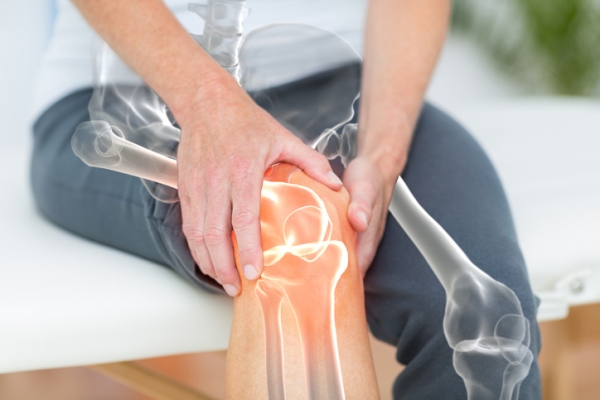

류마티스 관절염 치료법

초기에 발견되면 질병의 진행을 늦추는 약물 치료가 중심이 됩니다. 대표적으로 항류마티스제인 메토트렉세이트를 기본 치료제로 사용하며, 환자 상태에 따라 단기간의 스테로이드로 증상을 조절하기도 합니다. 부작용이나 반응이 좋지 않을 때는 다른 약제를 고려할 수 있으며, 설파살라진이나 기타 항류마티스제가 대안이 될 수 있습니다.

약물치료와 더불어 관절의 기능 보존과 통증 완화를 위해 재활치료와 규칙적인 운동을 병행하는 것이 권장됩니다. 관절 변형이 심하거나 통증 조절이 어려운 경우 수술적 치료(예: 활막 절제술 등)를 통해 증상을 개선할 수 있으며, 수술 후에도 적절한 재활과 운동으로 관절 강직을 예방해야 합니다.